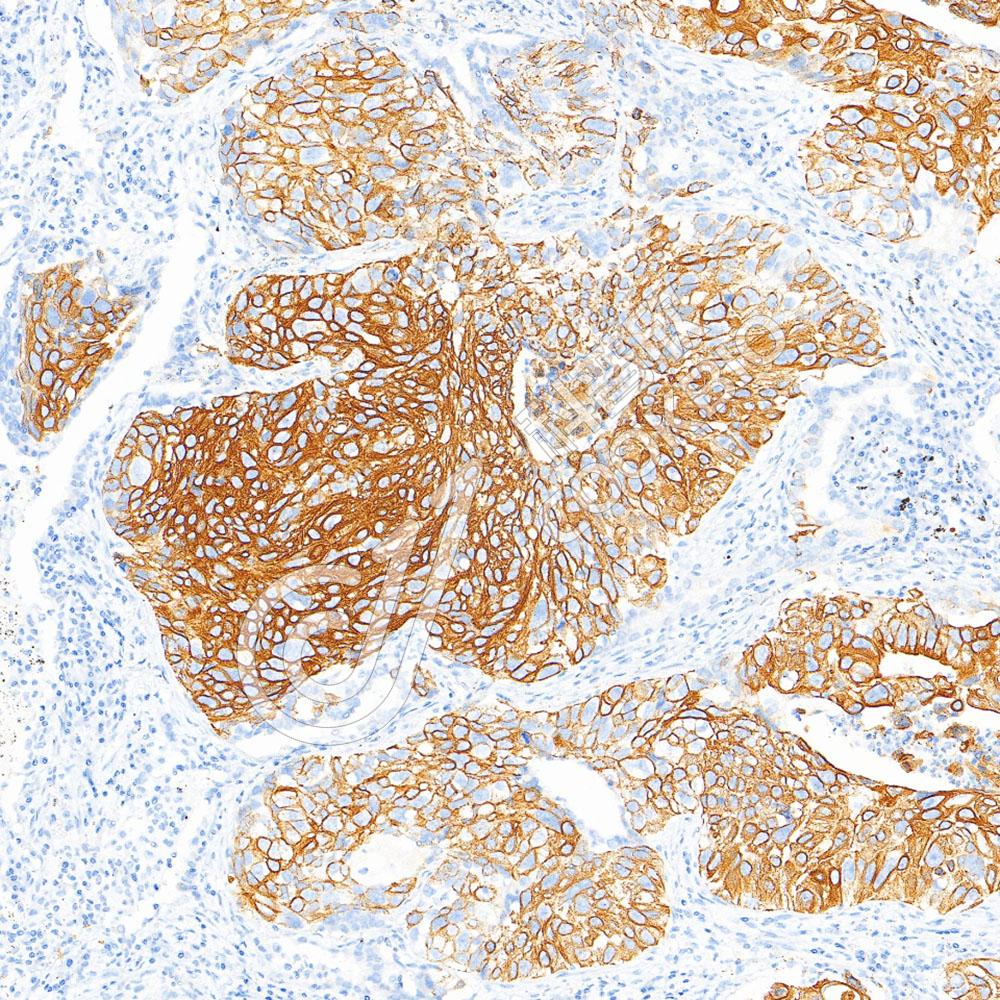

IHC检测Involucrin蛋白(货号 K1333504).

样品: 人扁桃体, 4%多聚甲醛 (货号KSG1101) 固定12-24小时.

抗原修复: 柠檬酸抗原修复液(干粉, pH 6.0) (KSG1201), 98℃, 20分钟.

—抗: 1: 2500稀释, 4℃ 孵育过夜.

二抗: S-vision免疫组化多聚二抗(山羊抗兔),即用型 (货号KB3906), 室温孵育20分钟.